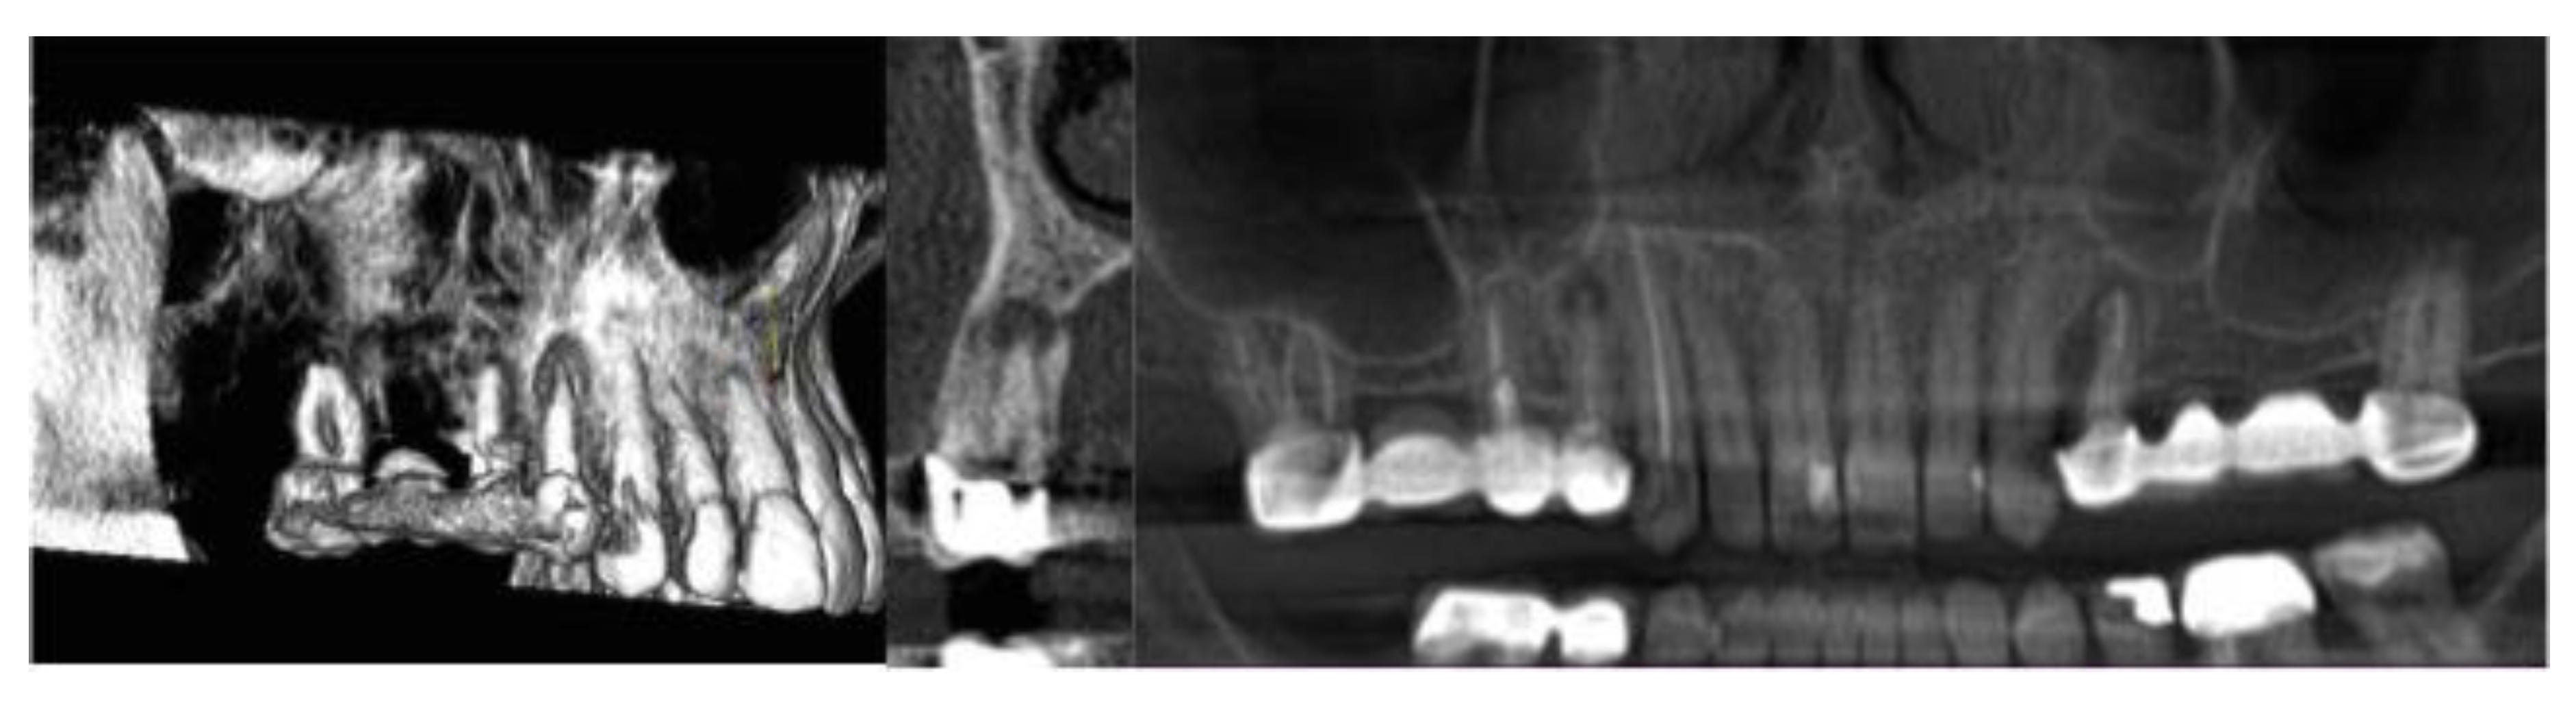

3D Assessment of Endodontic Lesions with a Low-Dose CBCT Protocol

2. Materials and Methods

3. Results